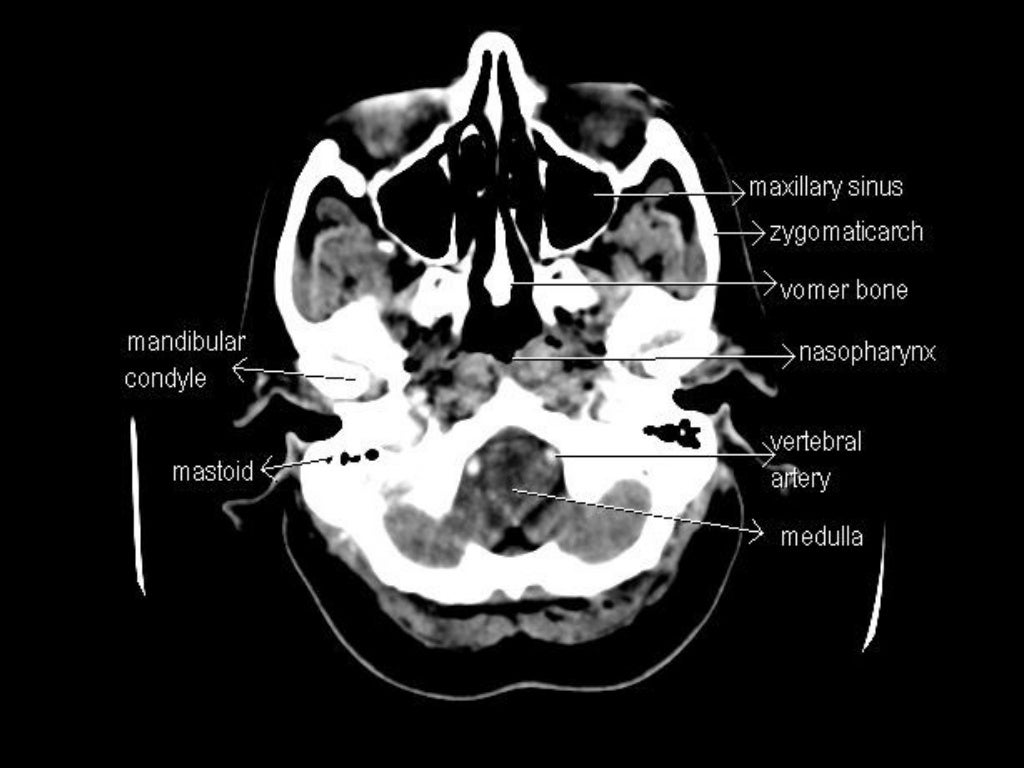

CT Anatomy

CT Scan Tips & Protocols CT BRAIN ANATOMY Ct Anatomy Of Brain Slideshare Anatomy of normal ct brain. Identify the ct anatomy of the brain 3. Review the basics of ct imaging 2. It describes the skull bones and sutures that. Ct scans are useful for. The document discusses the radiological anatomy of a normal ct brain scan. This document provides information about brain anatomy, including the embryology and major. Published by angelina. Ct Anatomy Of Brain Slideshare.

CT Anatomy Ct Anatomy Of Brain Slideshare It begins by describing the lobes of the brain and surfaces visible on ct. Anatomy of normal ct brain. This document provides an overview of the radiological anatomy of the brain through computed tomography (ct) imaging. Hounsfield units and densities of brain tissues on ct are defined. The document discusses the radiological anatomy of a normal ct brain scan. Ct. Ct Anatomy Of Brain Slideshare.

CT Anatomy Ct Anatomy Of Brain Slideshare Ct scans are useful for. Review the basics of ct imaging 2. The document discusses the radiological anatomy of a normal ct brain scan. Anatomy of normal ct brain. 1) the document provides an overview of the normal anatomical structures visible on ct scans of. Hounsfield units and densities of brain tissues on ct are defined. It describes the skull. Ct Anatomy Of Brain Slideshare.